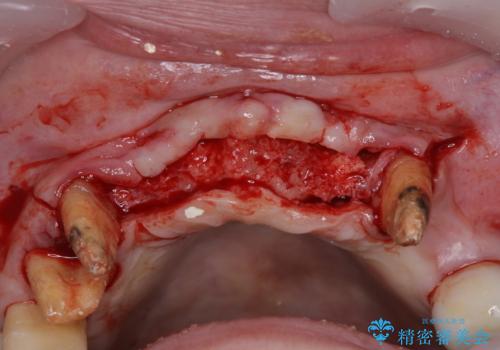

診査の結果、上顎奥歯を中心に深い歯周ポケットが認められたため、歯周ポケット除去を目的とした歯周外科処置を行うこととしました。

歯周外科処置を行ったことで歯周ポケットはなくなり、毎回のブラッシングの度に嫌な思いをしていた出血は認められなくなりました。